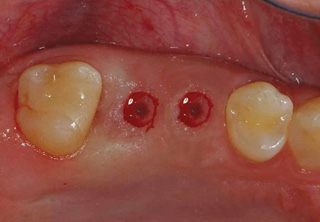

치주염 등으로 치조골(잇몸뼈)의 양이 부족한 경우

치조골 이식술을 통하여 충분한 뼈의 양을 확보한 후

임플란트를 식립합니다.

뼈의 밀도가 치밀하고 단단하며, 양이 충분할수록 임플란트의 성공률이 높아집니다.

청담네오플란트는 풍부한 경험의 의료진이 치조골 이식술을 통해 치조골을 적절한 양과

밀도로 재생시킨 후 임플란트를 식립합니다. 뼈의 흡수가 심하지 않아 적은 양의

치조골 이식을 하는 경우 임플란트 식립을 동시에 진행할 수 있지만, 뼈의 흡수가

심하여 많은 양의 치조골 이식이 필요한 경우 치조골 이식술을 먼저 진행한 후,

치조골이 재생되면 임플란트를 식립하여 보다 정밀하고 안전한 시술 결과를 얻을 수 있습니다.